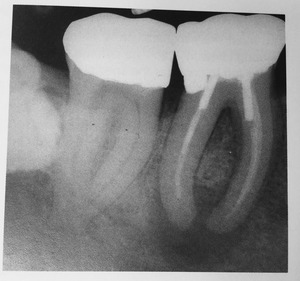

¥×¥é¡¼¥¯¥³¥ó¥È¥í¡¼¥ë¤Î¼£ÎÅÃæ¤Ç¤¹¡£